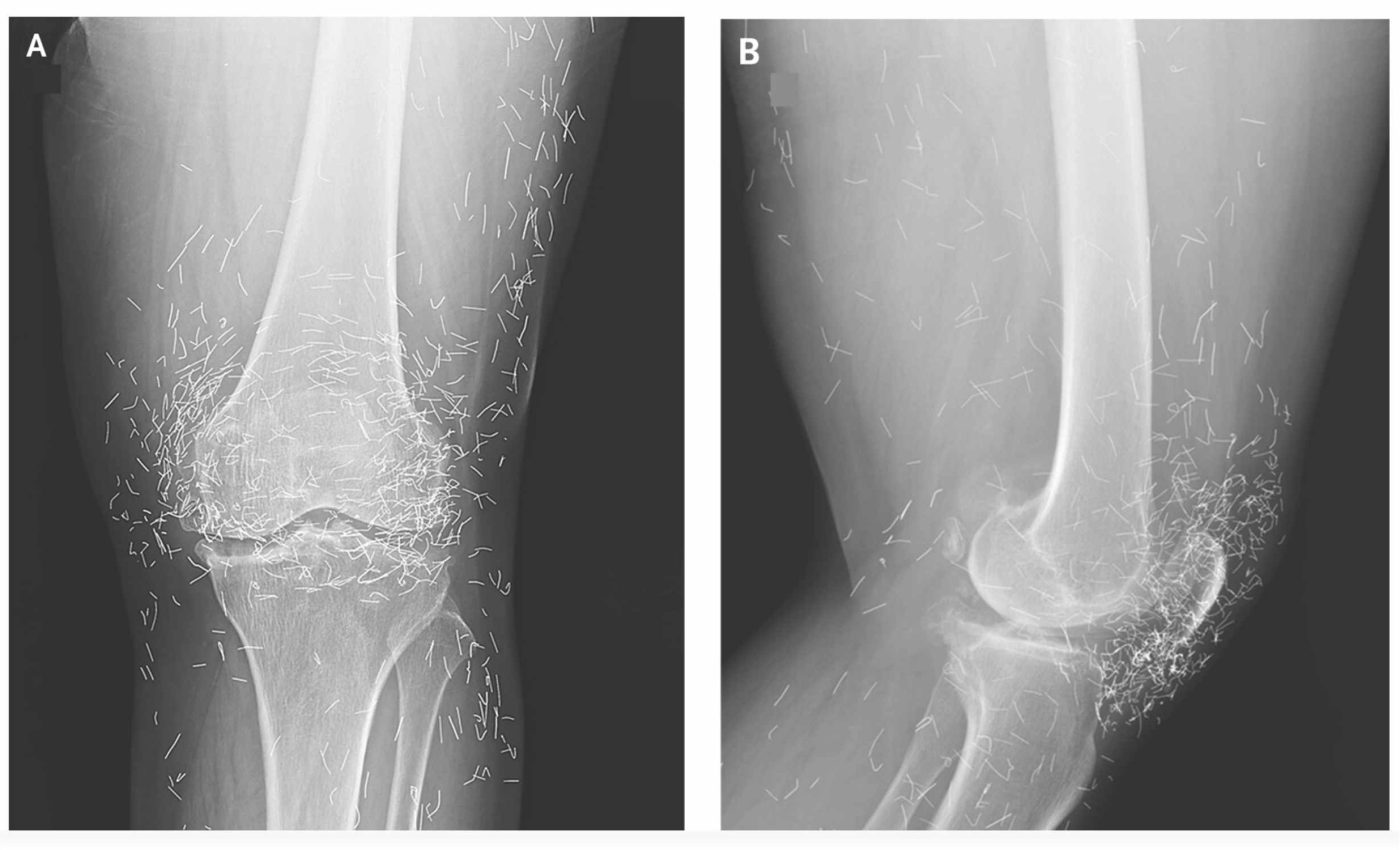

A 65-year-old woman in South Korea sought help for severe knee pain. Hospital X-rays showed hundreds of tiny gold threads surrounding the joint. The threads were intentionally left in place during gold-thread acupuncture, a technique that implants metal to extend stimulation.

In a clinical image case, radiographs showed thickened inner shin bone and prominent bony spurs near the joint.

Here subchondral sclerosis, hardening just below joint cartilage, appeared with narrowing of the medial joint space.

The images also revealed numerous radiodense strands clustered around the knee. Those lines are radiodense, bright on X-rays because metal strongly blocks the beam.

Gold threads add visual clutter that can mask edges used to judge wear and alignment. That can make precise grading of osteoarthritis, chronic joint cartilage loss that causes pain and stiffness, more challenging in busy clinics.